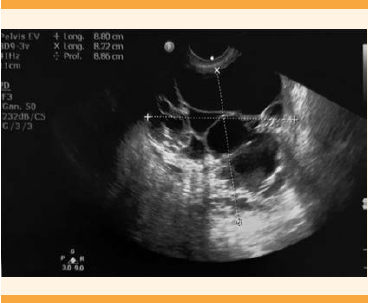

En la exploración física se encontró el abdomen blando, depresible, útero no delimitado, con anexo derecho aumentado de tamaño. En el ultrasonido pélvico se observó una tumoración en el anexo derecho, multiloculada, de aspecto complejo (Figura 1). La tomografía axial computada abdominopélvica reportó una lesión compleja, multiloculada, de paredes y septos gruesos, desplazamiento del útero hacia la izquierda, de aproximadamente 9.3 x 7.2 x 10.1 cm (Figuras 2 y 3). Se sospechó una tumoración de anexo, sobre todo dependiente del ovario. Por eso se solicitó la cuantificación del marcador tumoral Ca 125 que se reportó con valores dentro de límites normales. La citología cervicovaginal fue negativa para displasia.

Figura 1 Ultrasonido pélvico: anexo derecho multilobulado de 9 x 7 x 10 cm, ovario izquierdo normal.